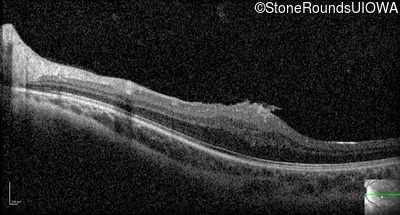

Optical Coherence Tomography - Left - 20/80

Exemplar / OCT Stack